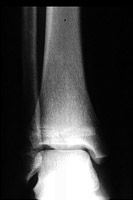

The triplane fracture is also known as the Marmor-Lynn fracture and typically occurs in adolescents. The term actually refers to three fractures of the tibia: a vertical fracture through the epiphysis, a horizontal fracture through the physis, and an oblique fracture through the metaphysis. Twisting injuries produce this type of fracture.

- Click on the image for a larger versionAAP radiograph of the ankle. The horizontal fracture through the lateral tibial physis is apparent as well as the vertical fracture through the epiphysis.